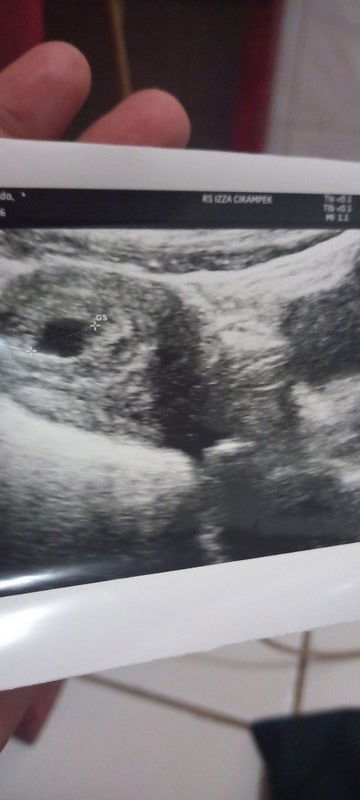

Assalamualaikum bun mau nanya klo kantung kehamilan sudah kurang baik kondisi nya apa bisa d selamat kan jujur tadi saya dengar dokter ngomong gini " Bu ini kantong nya udh rusak ? Terus saya tanya .. dok apa bisa d selamat kan. Dokter nya jawab "apa yg harus d selamat kn ini udh hilang kk ny di bagian bawah udh gepeng. Klo ibu masi penasaran kita bisa kasi penguat nanti tunggu 1 minggu kontrol tapi rata2 kebanyakan janin nya tidak akan berkembang. Jujur perkataan dokter bikin saya sakit bu Karna ini kehamilan ke 2 saya yg pertama juga keguguran. Sedangkan di rumah tidak ada dukungan keluarga bahkan suami saya seakan2 menyalahkan saya padahal saya seperti ini karna dia juga yg sudah menitipkan anak2 nya yg masi kecil umur 7 thn dan 15 bulan. Yg memangmereka sudah 2 hari ini sakit saya kurang tidur pusing karna yg kecil terus2 merengek. 😭 jujur bu saya sudah merasa putus asa saat ini saya harus apa?? ##bantusharing